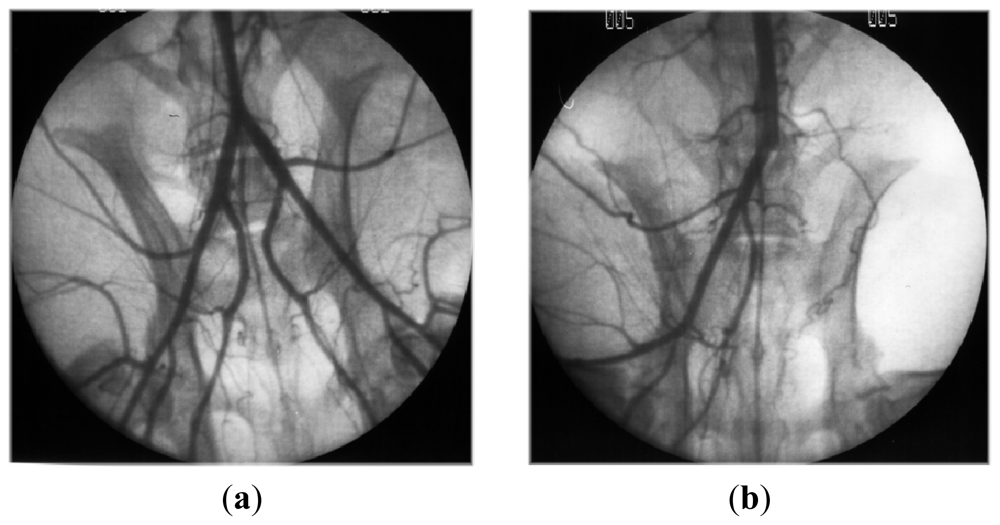

- Luyt, CE; Meddahi-Pelle, A; Ho-Tin-Noe, B; Colliec-Jouault, S; Guezennec, J; Louedec, L; Prats, HE; Jacob, MP; Osborne-Pellegrin, M; Letourneur, D; Michel, JB. Low-molecular-weight fucoidan promotes therapeutic revascularization in a rat model of critical hindlimb ischemia. J. Pharmacol. Exp. Ther 2003, 305, 24–30. [Google Scholar]

- Durand, E; Helley, D; Zen, AAH; Dujols, C; Bruneval, P; Colliec-Jouault, S; Fischer, AM; Lafont, A. Effect of low molecular weight fucoidan and low molecular weight heparin in a rabbit model of arterial thrombosis. J. Vasc. Res 2008, 45, 529–537. [Google Scholar]